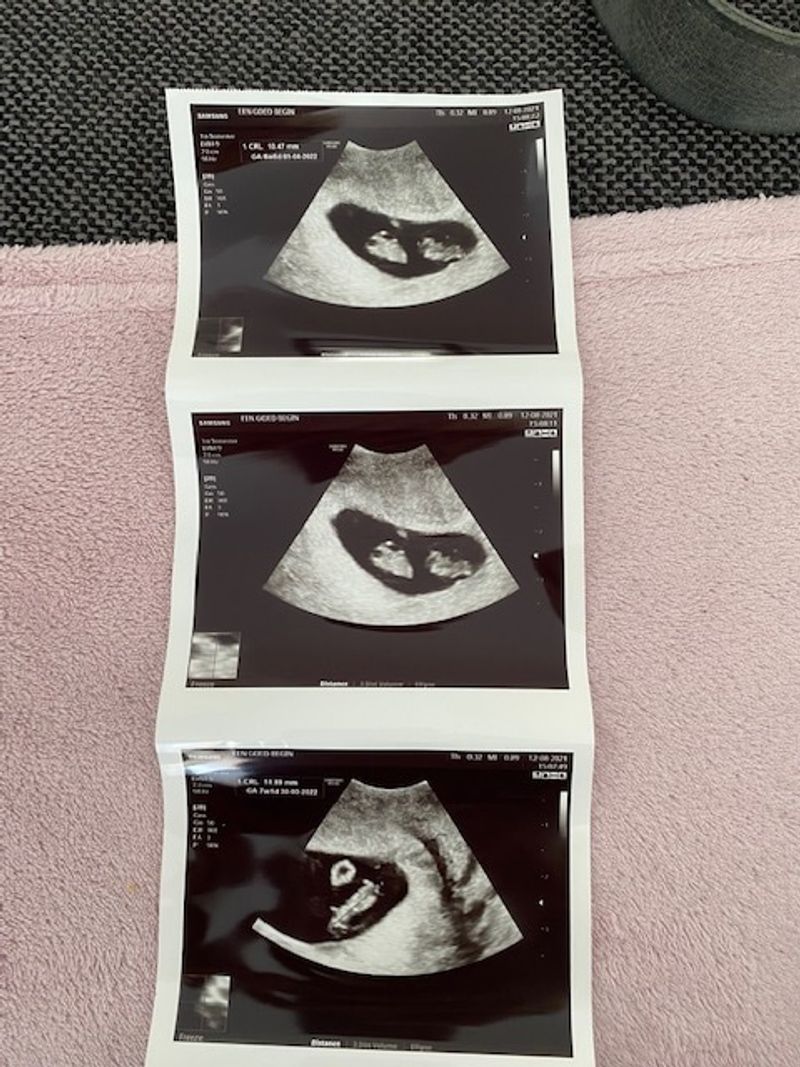

Lees eerst deel 1: Het bleek foute boel: kindje 1 had bijna geen vruchtwater meer en kindje 2 zwom in al het vruchtwater